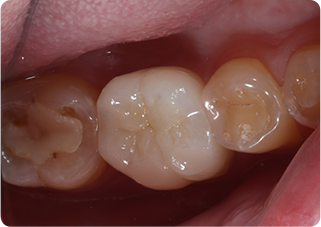

精密根管治療①

術前

術後

| 主訴 | 奥歯で噛むと痛い |

| 治療期間/回数 | 1ヵ月、3回 |

| 価格(税込) | 88,000円(税込) |

| リスク・副作用 | 病変再発、歯根破折の可能性 |

| ポイント | う蝕検知液を用い、むし歯の取り残しが無いようにし、ラバーダム防湿を行い、無菌的に根管治療を行った。根管充填材は、殺菌作用の強い保険適応外のMTAセメントを使用した。 |